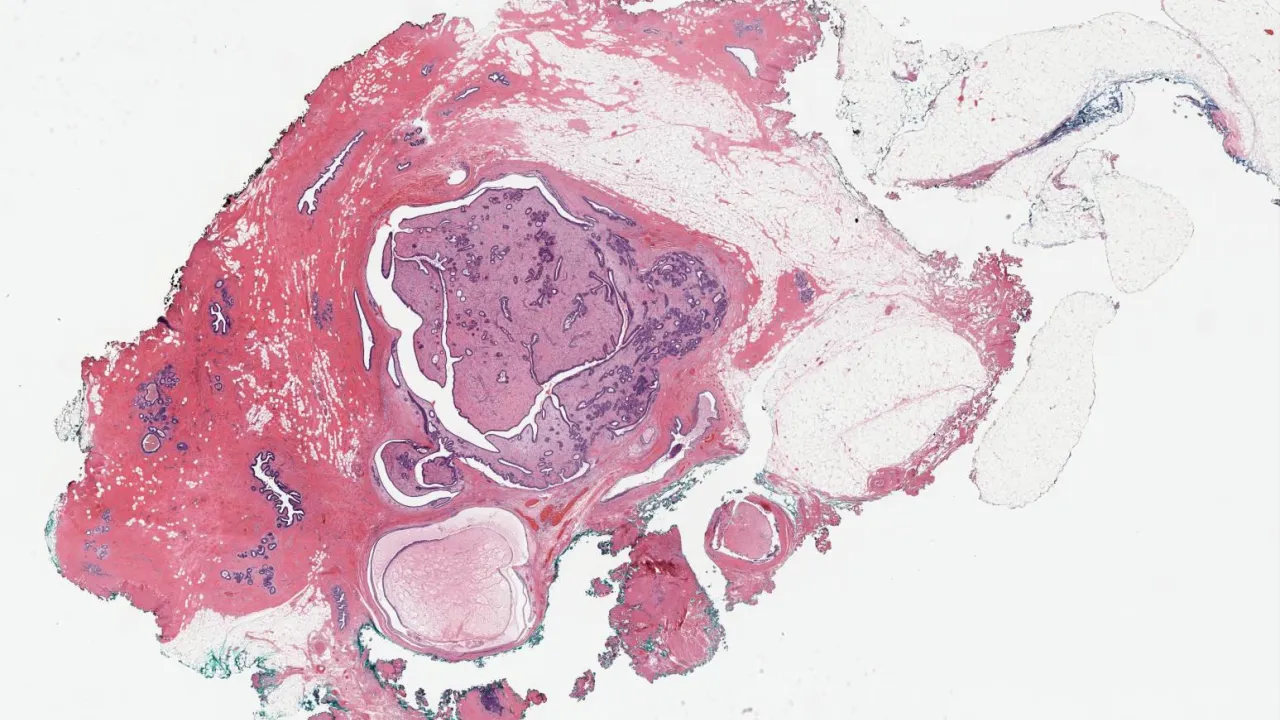

Brain, Angiomatous meningioma, CD34 stain

Brain, Angiomatous meningioma, D2-40 stain

Brain, Angiomatous meningioma, E-cadherin stain

Brain, Angiomatous meningioma, EMA stain

Brain, Angiomatous meningioma, H&E stain

Brain, Angiomatous meningioma, PR stain